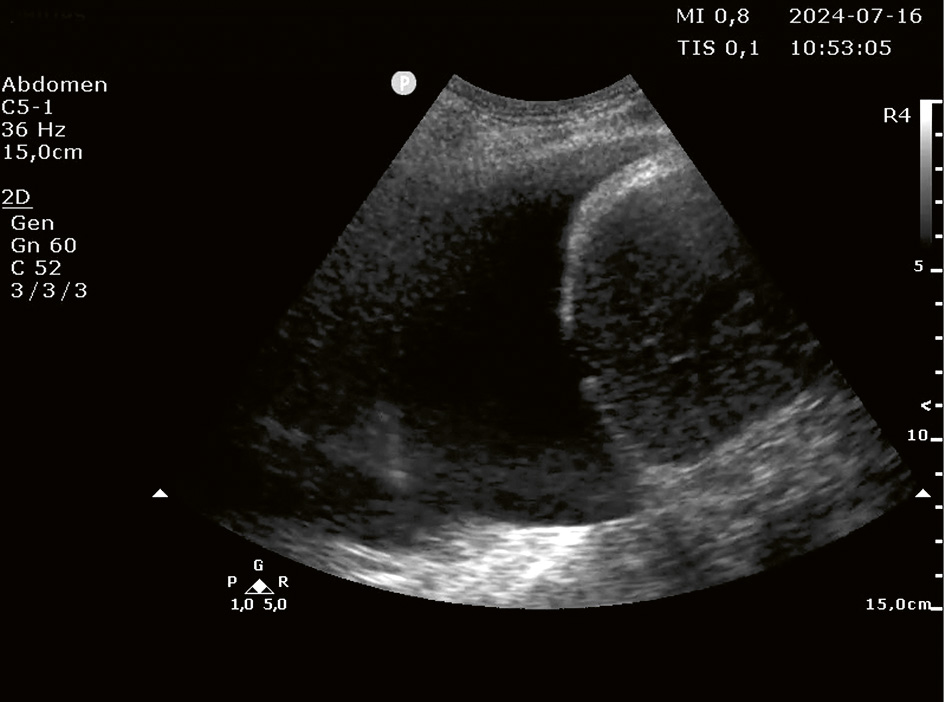

A. Insticksstället identifieras med hjärtprob. I bilden syns mjälten och diafragma (pil) till vänster om pleuravätskan (x). Insticksstället bör vara midaxillärt eller ventralt därom för att undvika trycksår när patienten ligger på rygg.

B. Operatören använder nu en mikrokonvex prob vid insticksstället. I bilden ses två revben (små pilar), diafragma (lång pil) och pleuravätska (x). Interkostala artärer kan ofta visualiseras kaudalt om respektive revben (y).